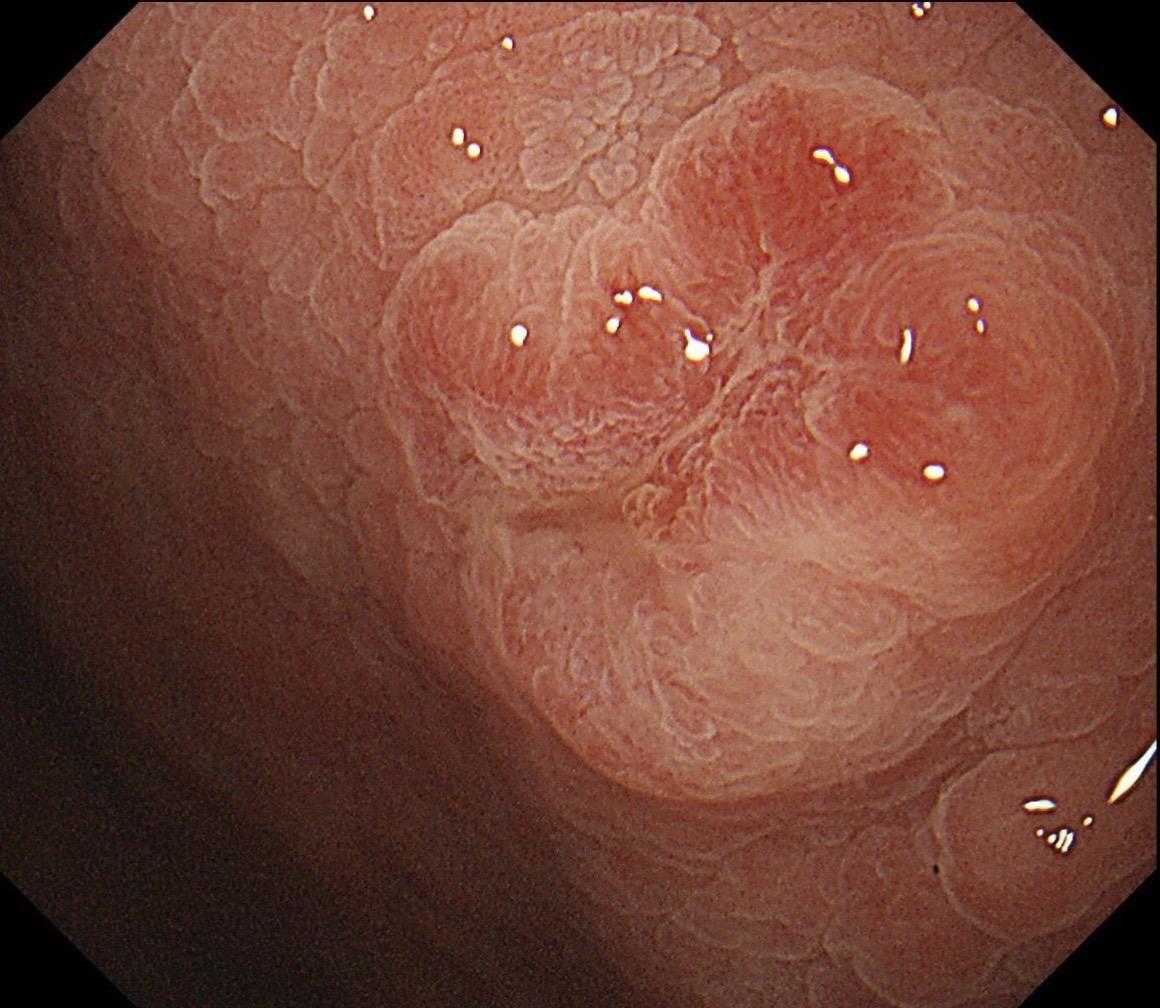

男,70岁,胃底体双发病变。看图猜猜病理呢……尤其胃底这个小的~凹陷性病变,当中央结构观察欠清时,边缘的异常微血管往往有提示作用,哪怕是局部。两处都考虑早期病变,拟ESD微创治疗。